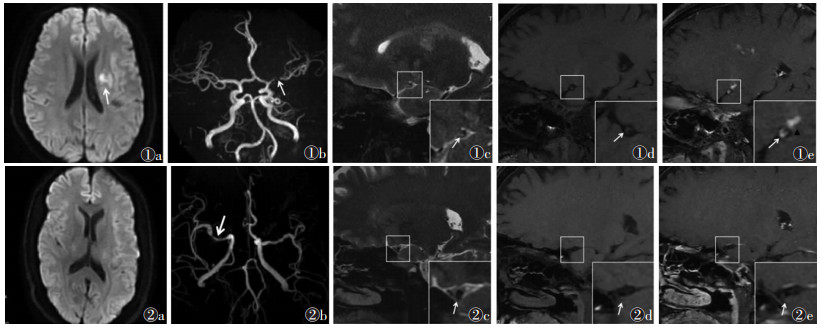

2.2 斑块特征42例共检出65枚斑块。急性脑梗死组20例,共33枚斑块(前循环21枚,后循环12枚),梗死灶位于放射冠或基底节区9例(图 1),颞叶或颞顶叶3例,脑干4例,小脑半球4例。非急性脑梗死组22例(图 2),共32枚斑块(前循环27枚,后循环5枚)。2组斑块位置差异无统计学意义(χ2=3.618,P=0.057)。急性脑梗死组的斑块T2WI信号和强化程度均显著高于非急性期脑梗死组,差异均有统计学意义(均P < 0.05);且急性脑梗死组的颅内动脉粥样硬化斑块多呈明显强化,而非急性脑梗死组多无明显强化(表 2)。二元Logistic回归分析显示,斑块T2WI高信号、明显强化是急性期脑梗死的独立危险因素(OR=16.41,P=0.004;OR=30.67,P=0.003)。

| 图 1 男,34岁,因“右侧肢体无力”入院 图 1a DWI序列显示左侧放射冠区斑片状高信号(白箭) 图 1b MRA示左侧大脑中动脉M1段局限性狭窄(白箭) 图 1c MR高分辨血管壁成像,选取管腔狭窄层面横轴位可见偏心性增厚斑块内部T2WI高信号(白箭) 图 1d T1WI序列上斑块呈等信号(白箭) 图 1e 高分辨血管壁成像增强扫描斑块明显强化(白箭),对应供血区域腔隙性脑梗死呈斑点状明显强化(黑三角) 图 2 男,54岁,因“头晕、恶性呕吐,肢体无力”入院 图 2a DWI序列未见高信号 图 2b MRA示右侧大脑中动脉M1段局限性狭窄(白箭) 图 2c 高分辨血管壁成像显示偏心性增厚斑块内部T2WI呈低信号(白箭) 图 2d T1WI序列上斑块呈等信号(白箭) 图 2e 高分辨血管壁成像增强扫描显示斑块无强化(白箭) |